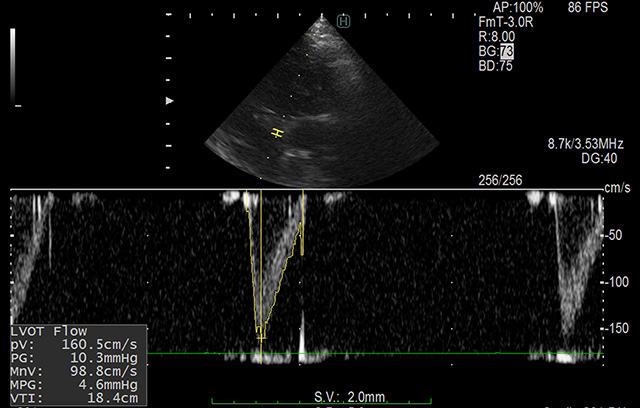

心臓の動きや血流をリアルタイムで捉える高度なエコー技術により、血液検査数値(バイオマーカー)だけでは分からない「心臓の真の状況」を把握します。

レントゲン、高解像度エコー、血圧測定、血液検査などを組み合わせ、心臓のサイズや機能を数値化します。